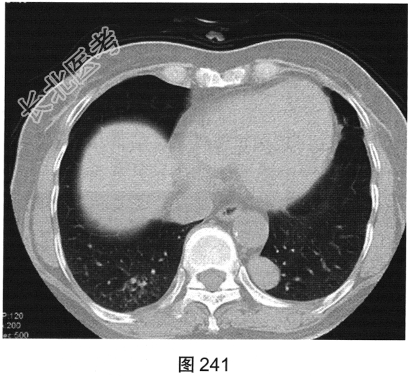

- [材料题] 患者女性,25岁。偶有胸闷,进食不畅,无咳嗽、无发热。行胸部CT检查,如图241、图242所示。

- 多项选择题1.对病灶的正确描述是( )

A、可见分叶

B、病灶位于左肺下叶内前基底段

C、病灶可能起源于左下后肋

D、胸膜凹陷征

E、宽基底于胸膜相连

F、病灶可能起源于胸膜

G、边缘光滑

H、病灶可能起源于椎管内